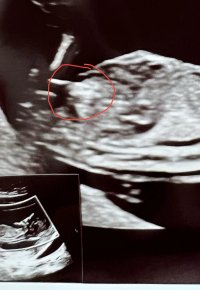

Det var i slik vinkel som bilde nr 2 her at min GY også gjetta på jente 12+3Synes ikke så godt her.. målt til 12+2 men gyn hadde en anelse ved bilde 2 der![]()

hu såg aldri etter "nub".